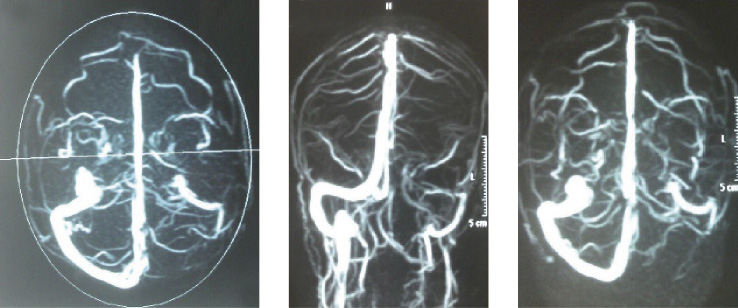

The MRI showed altered signal around the pineal gland without Fluid-Attenuated Inversion Recovery (FLAIR) signal suppression. The signal was judged possibly indicating a pineal cystis. Also, it showed alteration of the signal of the maxillary sinuses and turbinates of possibly inflammatory nature. The vMRA showed absence of the signal within the left transverse sinus and hypoplasia of sigmoid sinus and gulfs of the ipsilateral jugular (Figure 1).

Figure 1. Left transverse sinus absence shown by venous Magnetic Resonance Angiography (vMRA)

Considering the vMRA result, a hematological consult to perform a genetic trombophilic investigation was requested and a prothrombin mutation (G20210A) was detected. As a diagnostic conclusion, a secondary headache, headache probably attributed to consequences of cerebral venous thrombosis along with primary chronic migraine, was diagnosed in March 2014 [5]. At the same time, the prescribed therapy was therefore adjusted in light of the recent diagnostic change: thrombolysis and/or oral anticoagulant were not prescribed to the patient because it was not possible to temporally date the CVST onset; In facts, signal hyper-intensity, acute venous thrombosis marker, was not evident in the MRI T1 sequence. Therefore, the vMRA finding was judged as a probably old dated thrombosis outcome. After a consultation with the local hospital Hematology and Thrombosis Center, costs-benefits ratio wise, the anticoagulant therapy was considered inappropriate, since it was a long but undefined time ago dated thrombosis outcome. Topiramate (25 mg/day) was prescribed as a prophylactic therapy, while eletriptan (40 mg) was used as a once a need treatment. Moreover, the patient continued receiving BTXA (200 units per session) treatment every three months, being the next injection scheduled in April 2014. A follow-up program every three months after each injection session was planned. In June 2014, at the first follow-up examination (T2), the prolonged and pain increasing headache episodes were reduced to 2 episodes/month lasting one day. Pain intensity (NRS = 6) and degree of disability (MIDAS = 49) were also reduced. In September 2014, at the second follow-up examination (T3), headache frequency had reduced to 1 episode/month. Pain intensity was higher at onset (NRS = 8) and reduced in duration; degree of disability, while still high (MIDAS = 28), was also reduced (Figure 2, Figure 3). The patient will continue the BTXA treatment and the follow-up program at the Headache Center in Catanzaro. Monitoring time wise, the patient is adviced to undergo a yearly neuroradiological (vMRA) follow-up for 5 years, to monitor the venous obliteration state.